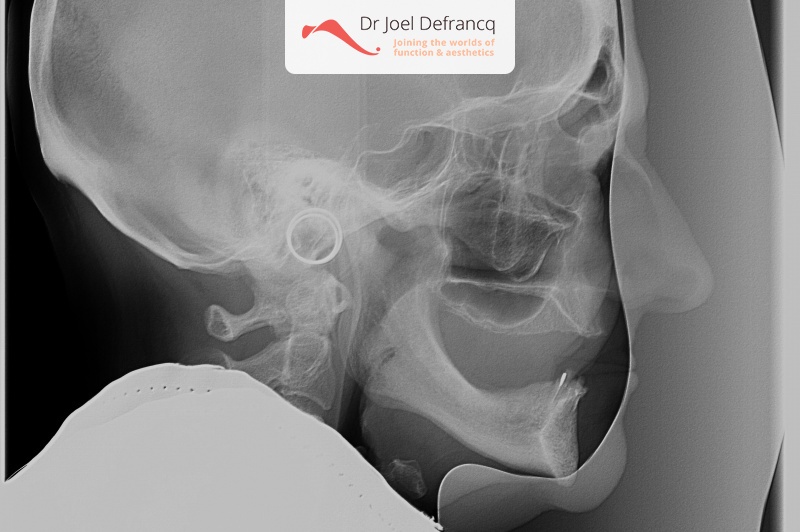

Vita: zygoma implants, all on four.

- Zygoma implantaten